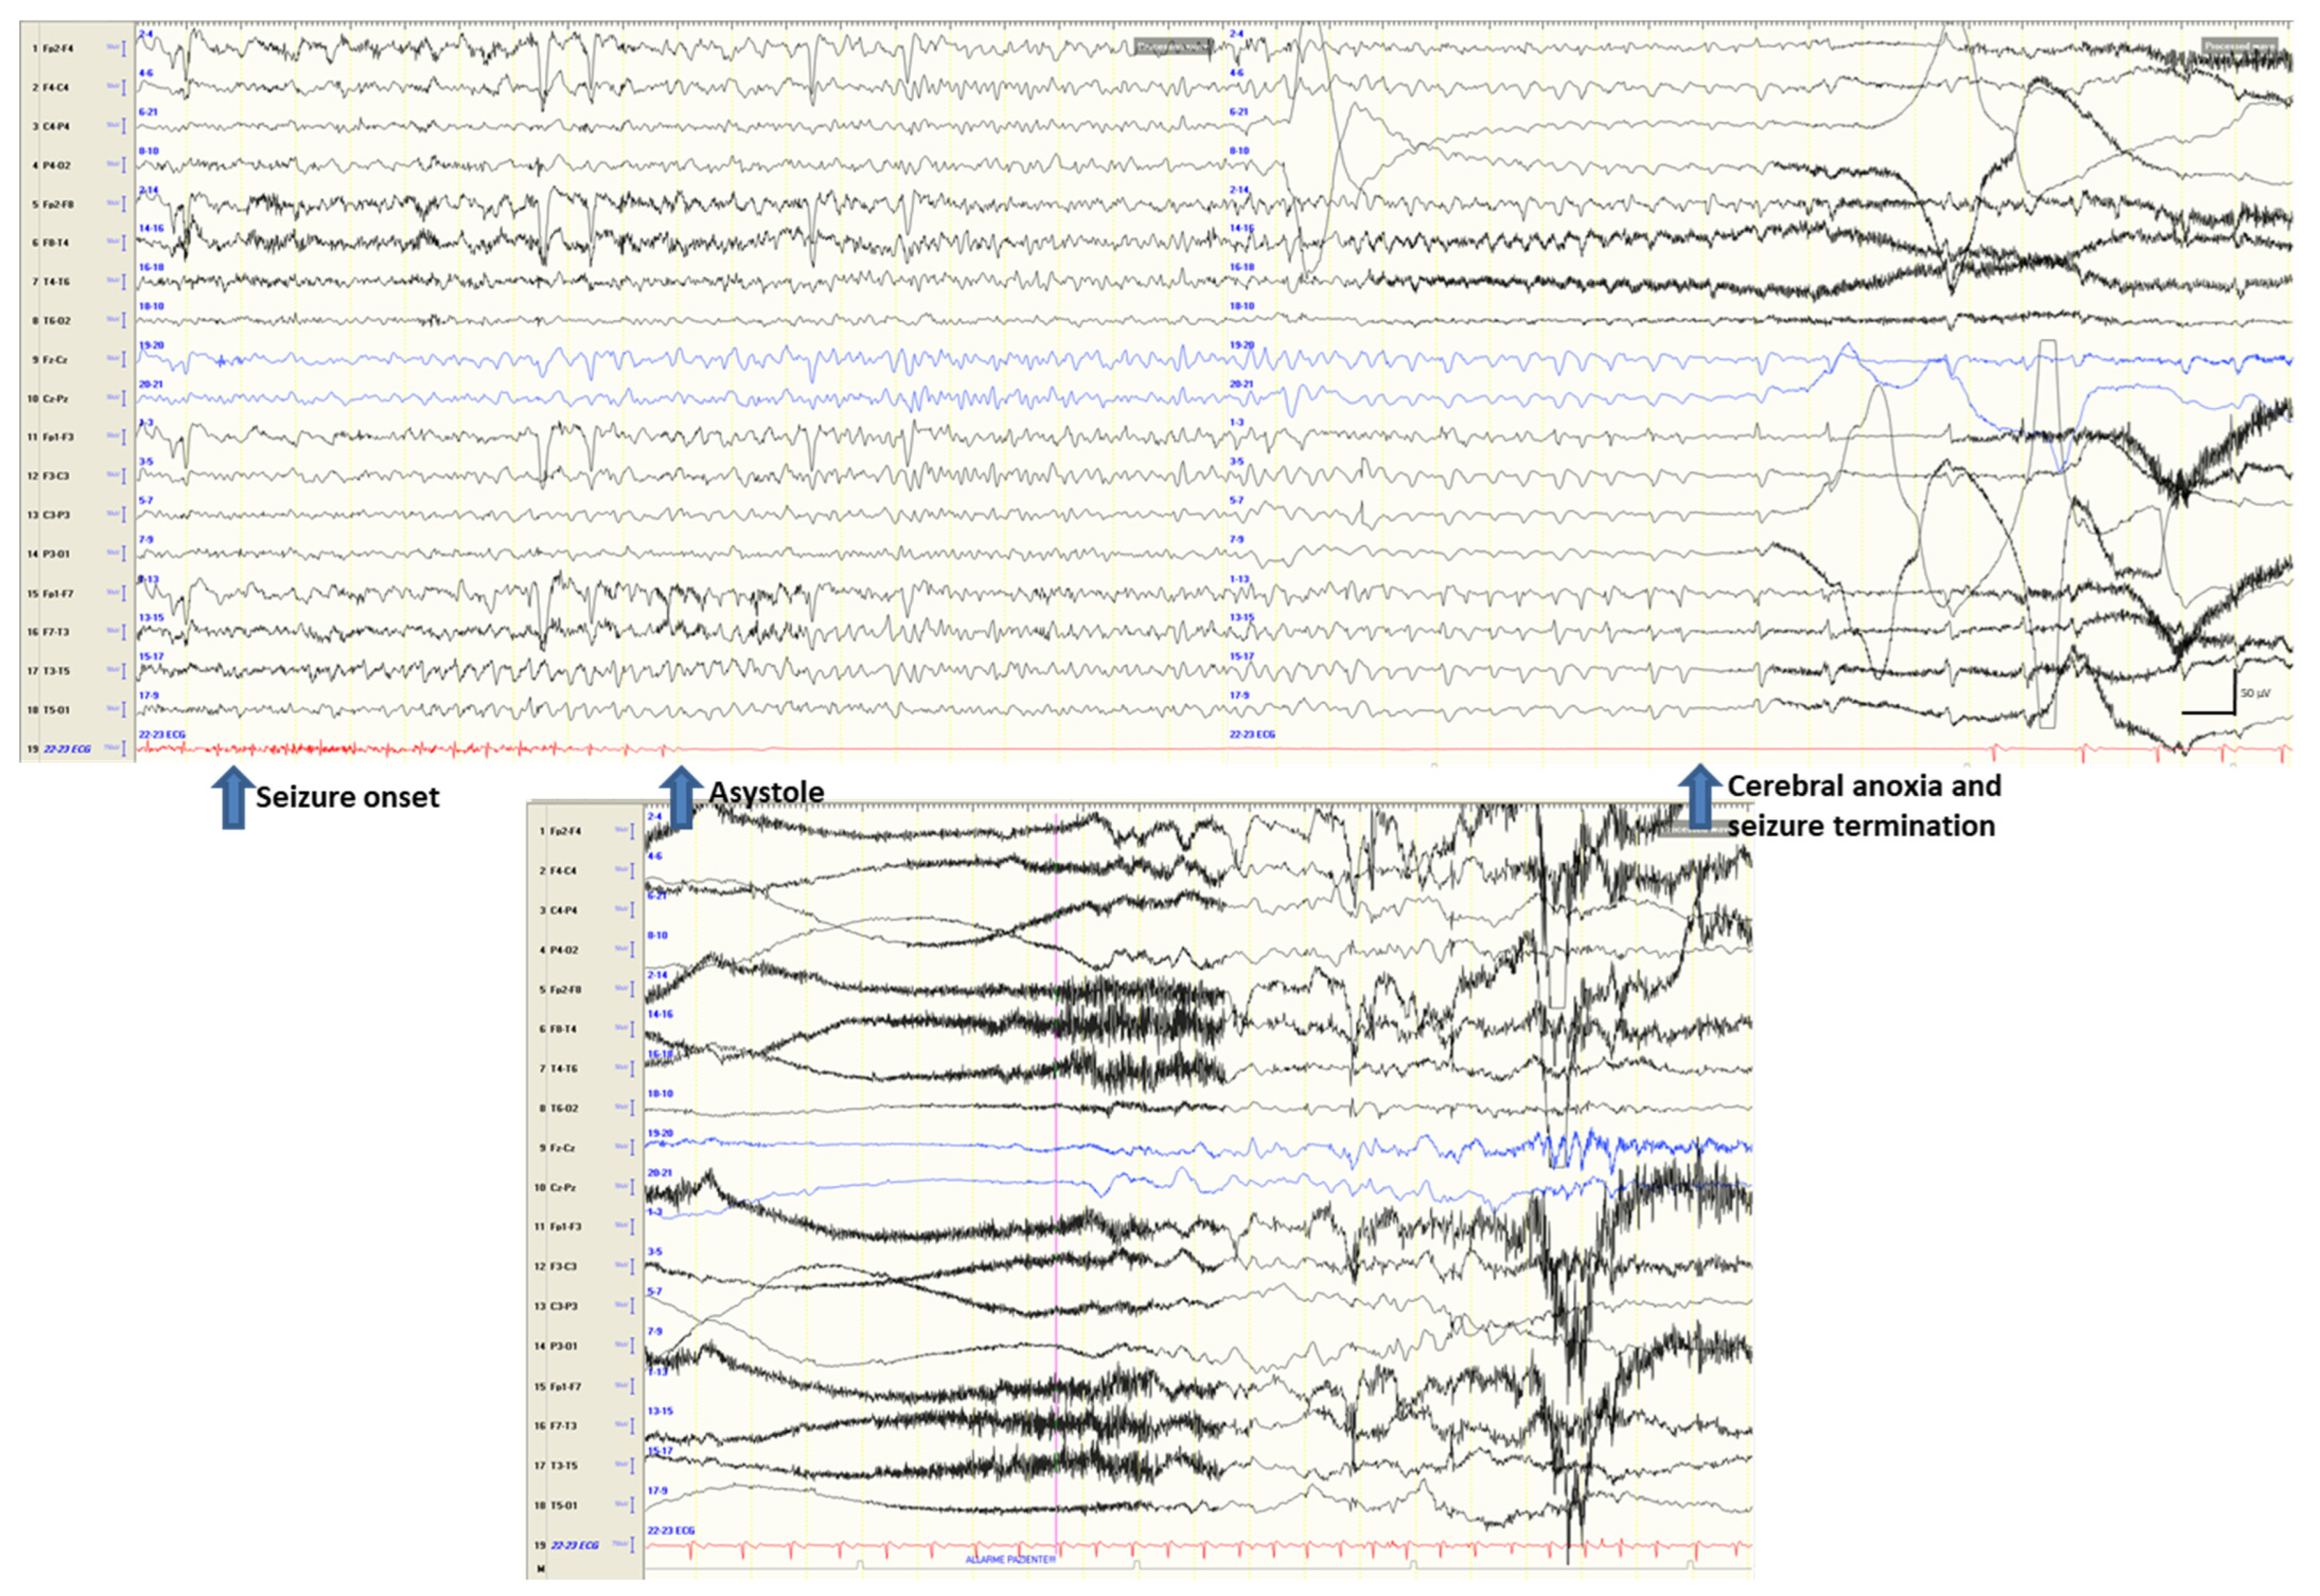

- Pasini, E.; Michelucci, R. Fit and faint or faint and fit? Clin. Neurophysiol. 2021, 132, 178–179. [Google Scholar] [CrossRef] [PubMed]